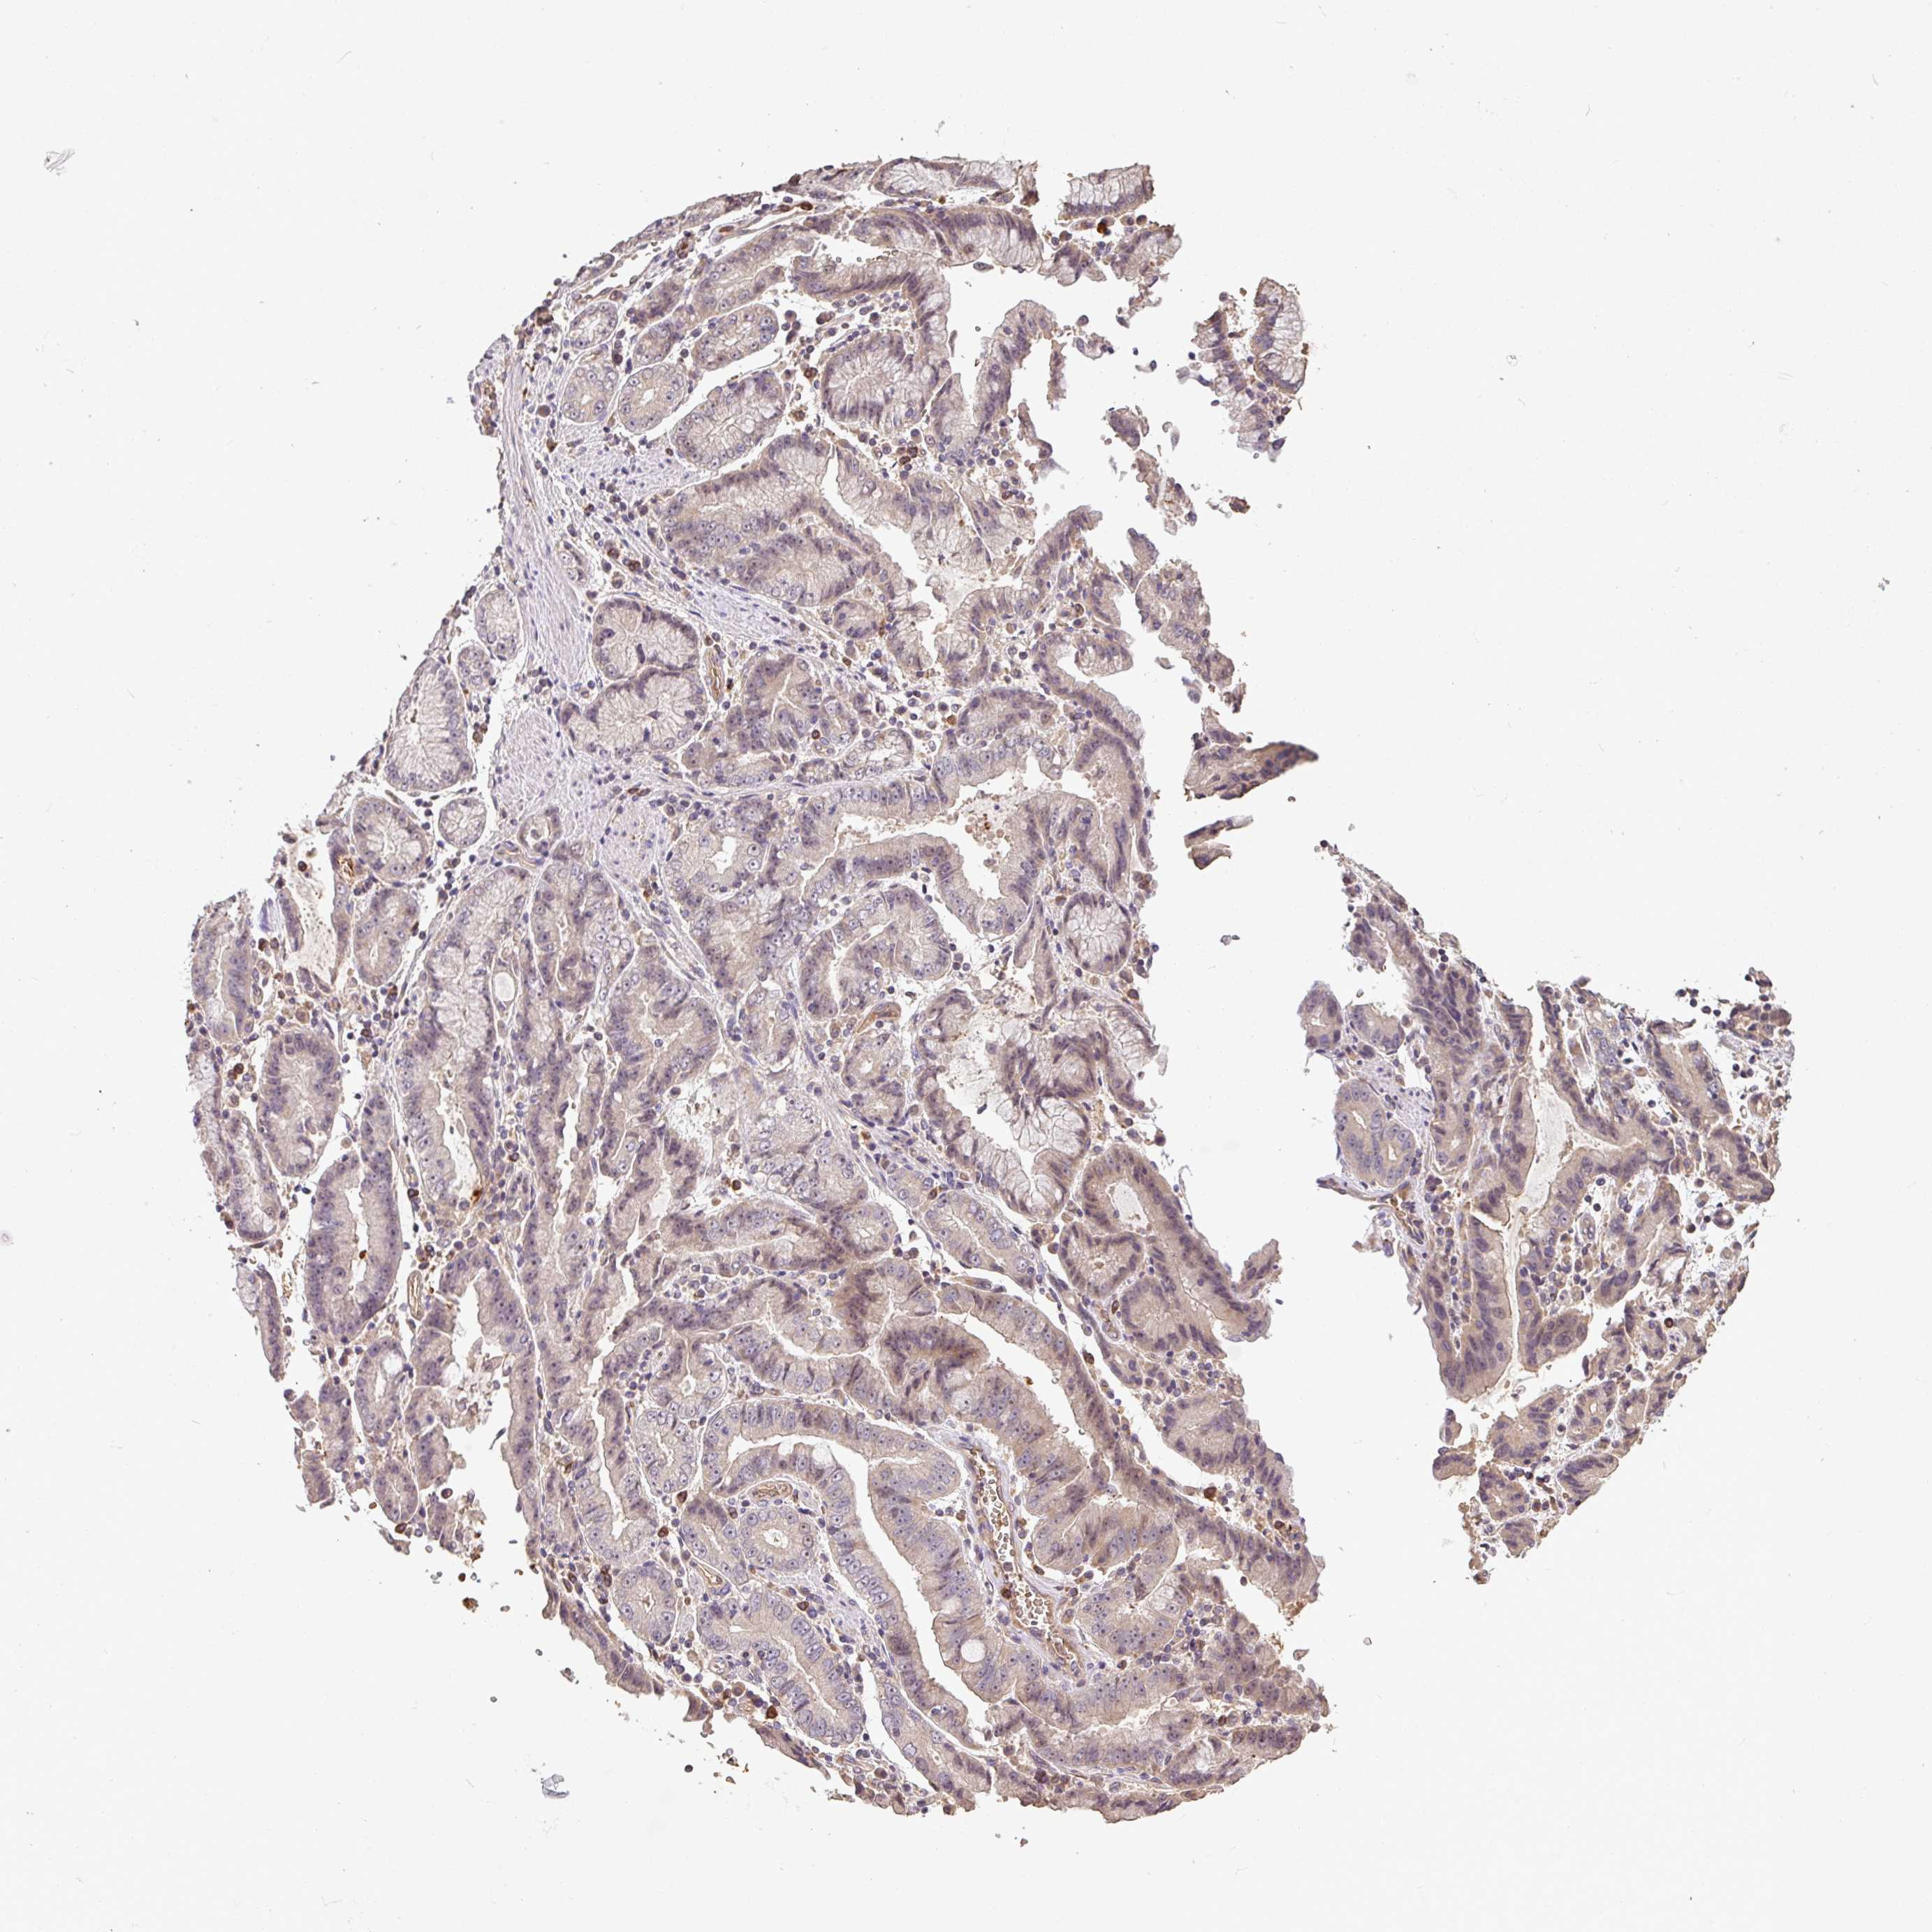

STOMACH CANCER - Protein expressioni

A mouse-over function shows sample information and annotation data. Click on an image to view it in a full screen mode. Samples can be filtered based on level of antibody staining by selecting one or several of the following categories: high, medium, low and not detected. The assay and annotation is described here.

Antibody stainingi

Antibody staining in the annotated cell types in the current human tissue is reported as not detected, low, medium, or high, based on conventional immunohistochemistry profiling in selected tissues. This score is based on the combination of the staining intensity and fraction of stained cells.

Each image is clickable and will lead to virtual microscopy that enables deeper exploration of all samples and also displays staining intensity scores, fraction scores and subcellular localization as well as patient and tissue information for each sample.

Antibody HPA056632

Staining

High

Medium

Low

Not detected

Intensity

Strong

Moderate

Weak

Negative

Quantity

>75%

75%-25%

<25%

None

Location

Nuclear

Cytoplasmic/membranous

Cytoplasmic/membranous,nuclear

Adenocarcinoma, NOS